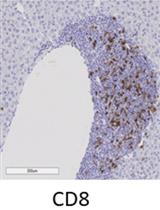

Immunohistochemical Staining of CD8α in Diabetic Mouse Kidney